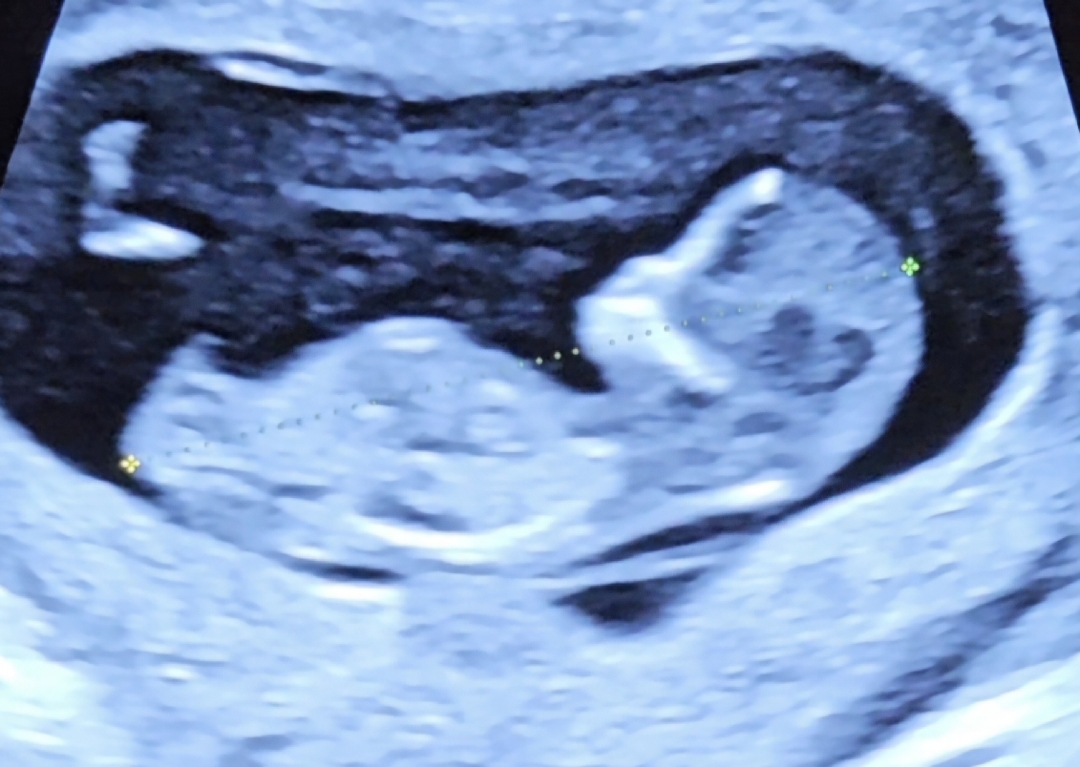

저는 11주차 2일인데 주수대비 애기가 커서 11주6일정도 된다고하던데.. 다른 11주차 사진대비 팔다리가 훅 큰 느낌이네요..😅 성별 궁금해서 찾다보니 각도법?이라는게 있는걸 첨 알았어요! 고수님들 혹시 뭘로 보이시나용? 알려주세요😁